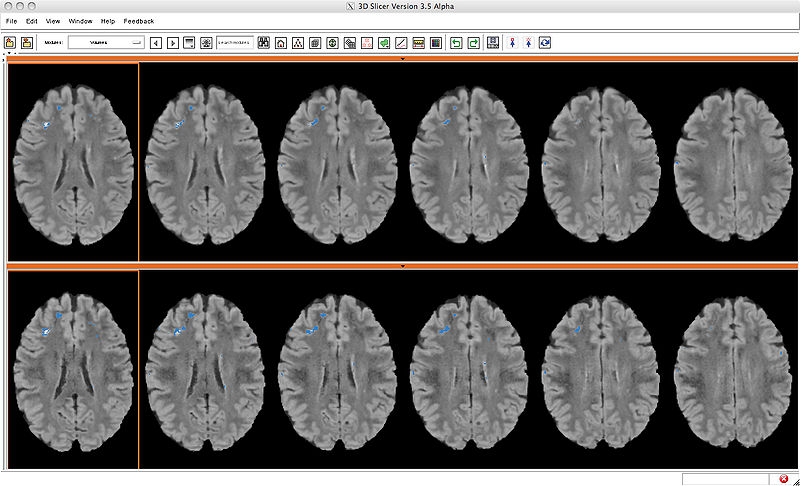

Compare Layout overview of difference between baseline and followup of lupus lesion subject with independent lesion segmentations

| current | 17:43, 13 May 2010 | 1,440 × 874 (473 KB) | Mscully (talk | contribs) | Compare Layout overview of difference between baseline and followup of lupus lesion subject with independent lesion segmentations |